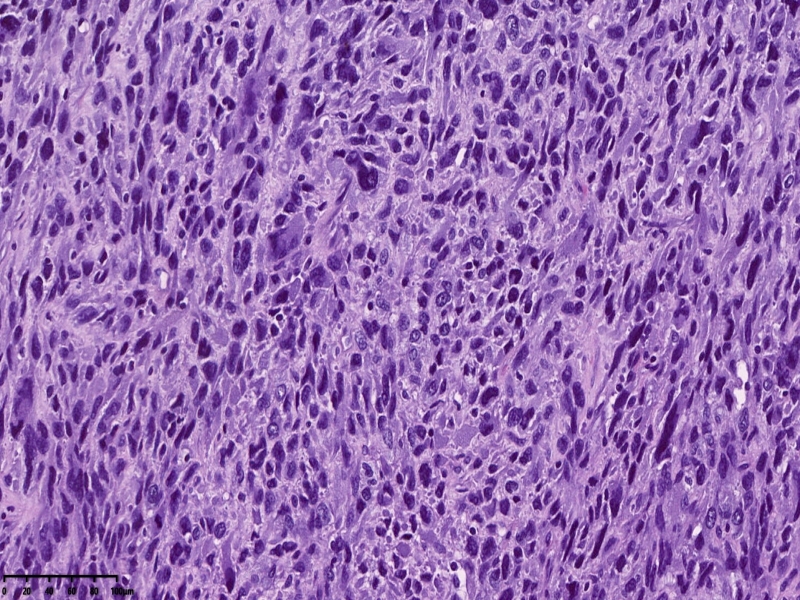

镜下可见肌间可见梭形瘤细胞,细胞核畸形,多核瘤巨细胞。坏死。